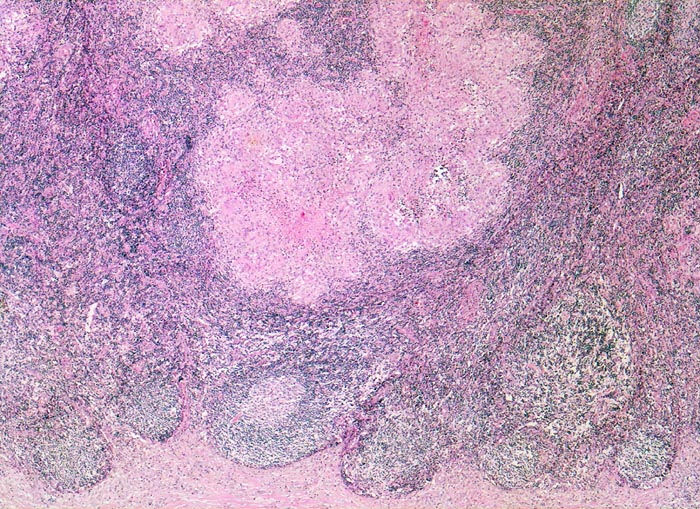

In der mittleren Dermis bilden sich Nekroseareale, welche von palisadierenden Histiozyten, mehrkernigen Riesenzellen und eosinophilen Granulozyten demarkiert werden. Die regionären Lymphknoten zeigen ebenfalls eine retikulozytär abszedierende Entzündung. Diese ist jedoch nicht spezifisch. Sie kommt auch vor bei Yersiniose, atypischer Mykobakteriose, Sporotrichose, Tularämie, Tumoren, Lymphogranuloma venereum und Coccidiomykose.

• Girlandenförmige basophile Nekrosezonen durchsetzt von neutrophilen Granulozyten (abszedierende Entzündung).

• Demarkierung der Abszesse durch palisadenförmig angeordnete epitheloide Histiozyten (heller Randwall um die Abszesse).